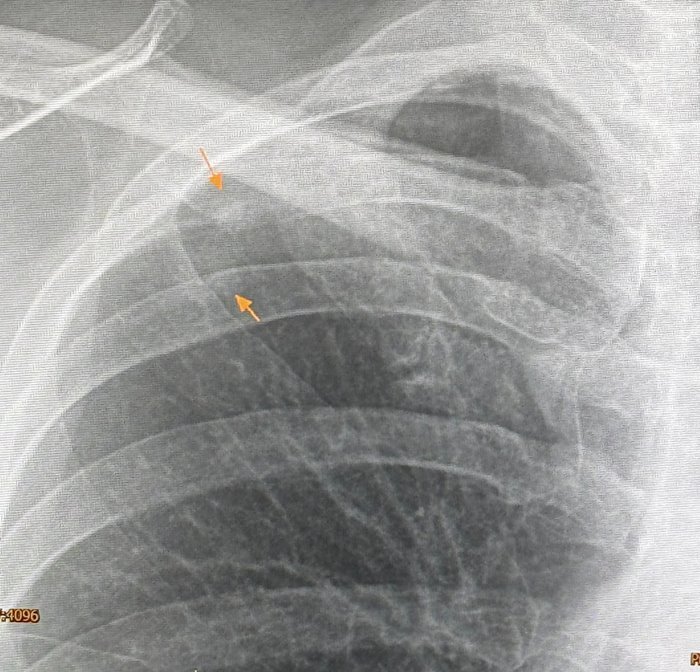

วันที่ 3 มิถุนายน 2567 นพ.มนูญ ลีเชวงวงศ์ แพทย์เฉพาะทางด้านโรคระบบการหายใจ โรงพยาบาลวิชัยยุทธ โพสต์ผ่านเฟซบุ๊ก หมอมนูญ ลีเชวงวงศ์ FC ระบุว่า พบเคสผู้ป่วยหญิงอายุ 52 ปี บ้านอยู่ กทม. ปกติแข็งแรงดี ไม่ไอ ไม่มีไข้ ไม่เบื่ออาหาร น้ำหนักไม่ลด ไม่ปวดหัว ไม่เคยสูบบุหรี่ ไม่มีโรคประจำตัว ไปตรวจร่างกายประจำปี เมื่อ 12 พฤษภาคม ที่ผ่านมา เอกซเรย์ปอดพบก้อนเล็ก ๆ เกิดขึ้นใหม่ที่ปอดขวากลีบบน

เอกซเรย์ปอดก่อนหน้านั้น 1 ปีปกติ ทำคอมพิวเตอร์ปอดพบก้อนขนาด 0.9 × 0.9 × 1.7 เซนติเมตร เห็นโพรงอยู่ข้างในก้อนที่ปอดขวากลีบบน ตรวจเลือดไม่ติดเชื้อเอชไอวี